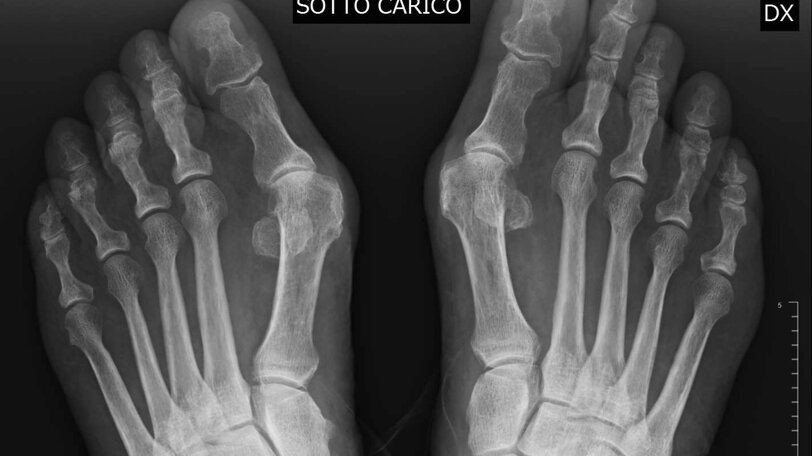

L'alluce valgo e' la piu' comune affezione dell'avampiede ed e' caratterizzata dalla deviazione laterale dell'alluce a livello dell'articolazione metatarso-falangea associata ad un aumento dell'angolo tra primo e secondo metatarso (varismo del I metatarso), alla lussazione dei sesamoidi ed alla protrusione dell'eminenza mediale. Puo' essere causato da molti fattori. Tra i fattori intrinseci e' fondamentale la componente genetica, infatti piu' del 60% degli affetti presenta casi analoghi in famiglia. Le calzature sono la principale causa estrinseca, in particolare se con tomaia stretta e tacco alto. Anche il piede piatto puo' predisporre all'alluce valgo. Il paziente lamenta dolore in corrispondenza dell'esostosi ed al di sotto della prima articolazione metatarso-falangea, il dolore aumenta con la scarpa indossata. Spesso puo' essere associato ad arrossamento e tumefazione. L'esame principale e' rappresentato dalle radiografie dei piedi sotto carico nelle due proiezioni, utilizzate per misurare i vari parametri, che contribuiscono a guidare nella scelta del tipo di trattamento da adottare. Gli obiettivi dell'intervento comprendono il sollievo del dolore con una correzione della deformita' ed il ripristino della corretta biomeccanica dell'articolazione. Gli interventi di correzione possono agire solo sulle parti molli, interessare il primo metatarso, o esclusivamente la falange prossimale dell'alluce. Nei casi piu' gravi si puo' ricorrere all'artrodesi, bloccando l'articolazione. Nel periodo post-operatorio il carico e' concesso immediatamente con una calzatura particolare che consente l'appoggio sul retropiede. I pazienti vengono controllati una volta a settimana per la medicazione della ferita chirurgica ed il rinnovo del bendaggio, che dovra' essere mantenuto all'incirca per 6 settimane. Tale periodo varia in funzione del tipo di tecnica adottata per la correzione.